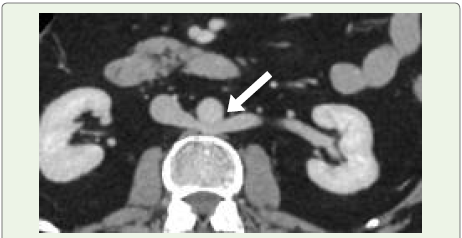

Portal Biliopathy:

Portal biliopathy refers to a collection of abnormalities affecting

the bile ducts and gallbladder, typically seen in individuals with

extrahepatic portal vein obstruction or portal hypertension [31].The condition arises primarily through two mechanisms: first, by direct mechanical pressure on the biliary tract from a portal cavernoma [Figure 12] and second, through peribiliary fibrosis triggered by inflammation or ischemia following thrombosis in the

Figure 12:A 55-year-old woman diagnosed with portal hypertension. (A) Axial

contrast-enhanced CT image reveals cavernous transformation of the portal

vein (white arrow). (B) Coronal contrast-enhanced CT scan shows dilated

biliary ducts (black arrow) secondary to external compression from the portal

cavernoma (white arrow), indicative of portal biliopathy.

small venous channels within the bile duct wall [4,9,32]. A portal

cavernoma is a network of dilated collateral veins surrounding the

common bile duct, resulting from cavernous transformation. It is

composed of paracholedochal veins (also known as the plexus of

Petren) and epicholedochal veins (plexus of Saint), both of which run

along the bile duct wall [33].

There are three main types of portal biliopathy: varicoid, fibrotic,

and mixed. The varicoid form is due to compression and distortion

of the bile duct by large external collaterals (paracholedochal veins),

while the fibrotic form is associated with thickening and narrowing

of the bile duct caused by intramural compression from smaller

collateral veins (epicholedochal veins) [4].

or jaundice [4,9,31].Imaging findings:

Contrast-enhanced CT is typically performed to rule out

alternative causes of biliary dilation, especially since portal biliopathy

can resemble malignant distal bile duct strictures, such as those from

pancreatic cancer or cholangiocarcinoma [34]. The most characteristic

radiologic sign, apart from detecting a portal cavernoma, is the

abrupt bending or “kinking” of the common bile duct, usually due to